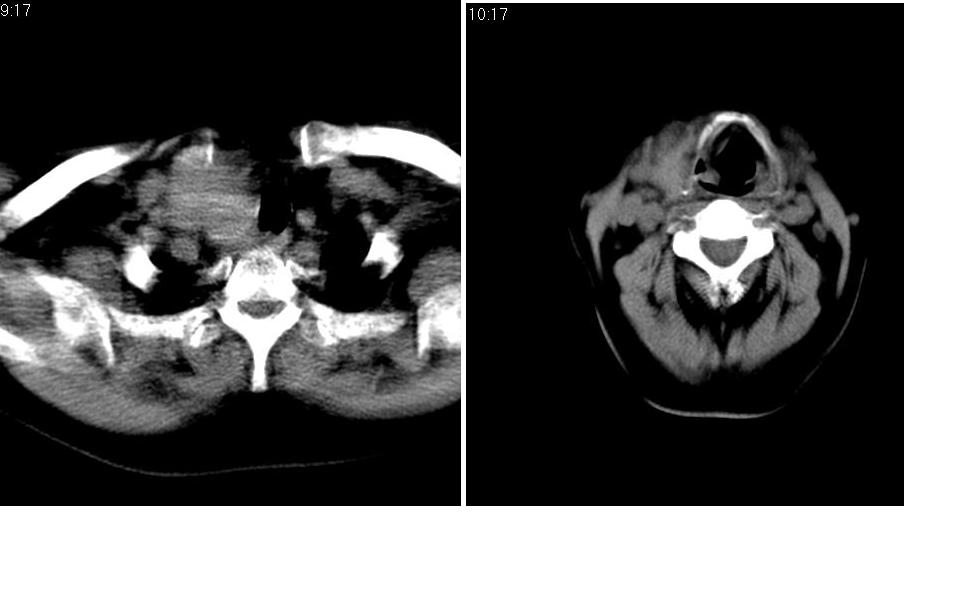

女 55岁 右侧颈部包块十年余,自己感觉有增大。

右侧甲状腺癌或腺瘤。

边缘清晰光滑,偏向于甲状腺瘤。

来源于右侧甲状腺  边界清晰,内可见点状钙化,向下生长达前上纵隔血管间隙内  考虑甲状腺腺瘤并胸内甲状腺肿

甲状腺瘤可能性大!建议强化!

右侧甲状腺区占位(腺瘤?),建议同位素扫描。